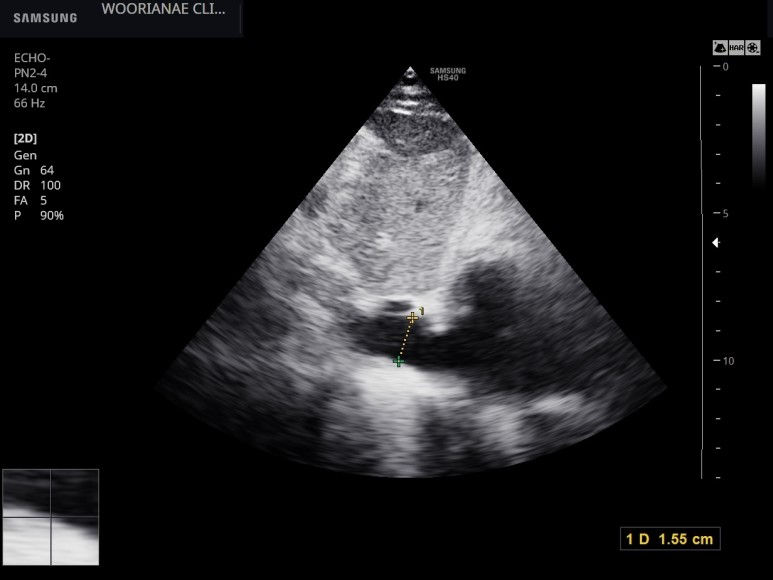

4일뒤 심장 초음파 시행

심실벽의 전반적인 비대, septum은 16.3 mm

수축기 기능은 여러번의 측정에 40~45% 범위, 경도~중등도로 감소되어 있다.

심실벽 운동은 대칭적으로 전반적인 움직임 감소